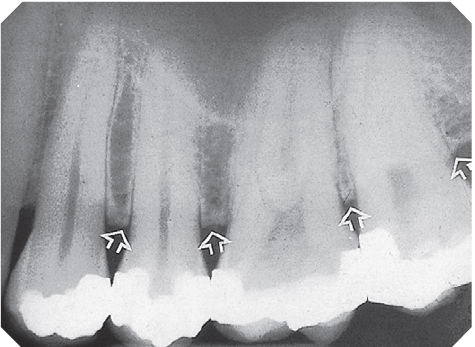

31. What arrow shows?

32. What is showing by the arrow?